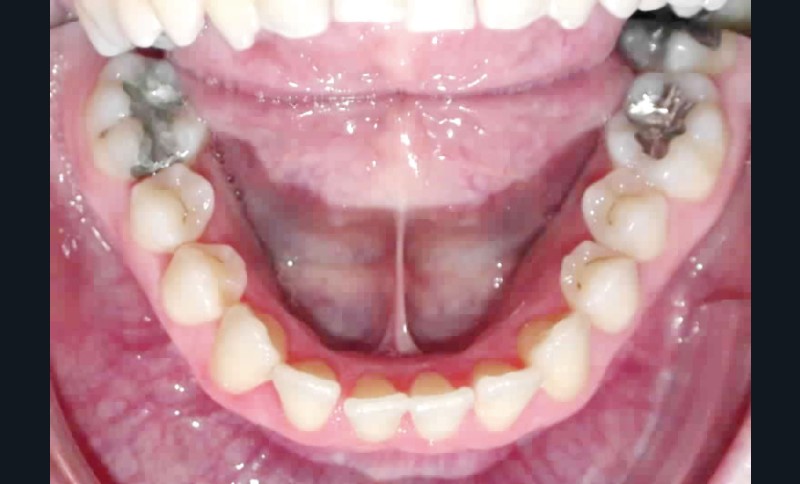

Cette patiente est venue consulter pour son occlusion inversée et ses importantes malpositions dentaires antérieures associées à la perte d’une dent et à des problèmes parodontaux.

• Malocclusion de classe III d’Angle par rétroalvéolie maxillaire,

• endoalvéolie maxillaire avec occlusion inversée antérieure et bilatérale,

• infraclusion incisive,

• fortes malpositions des incisives supérieures (dont 22 qui est en rotation axiale disto-palatine de 90°), • dysharmonie dento-dentaire (12 en « grain de riz » est aussi en rotation marginale disto-palatine de 45°),

• anomalie de la forme d’arcade maxillaire, 47, 18 et 28 sont absentes. (fig. 1 à 8), 48 est positionnée très postérieurement, quasiment au niveau de la branche montante (fig. 9 et 11).

Sur le plan parodontal, il existe une gingivite résiduelle à une gingivectomie (la patiente étant sous anti-épileptiques).